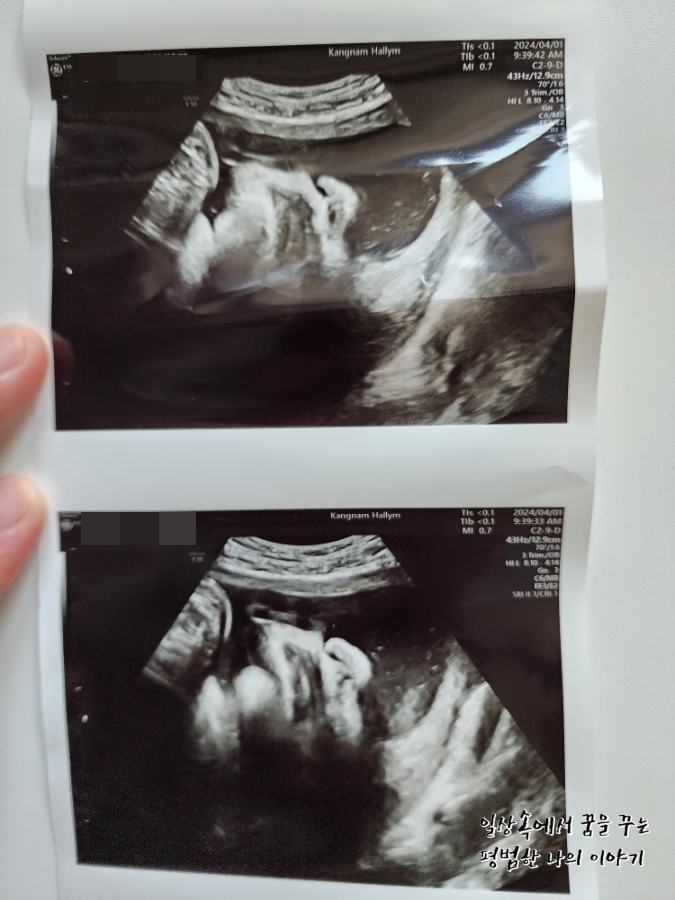

2024년 4월 1일(월요일)

BPD(Biparietal Diameter, 위에서 볼 때 태아 머리 단면의 가장 긴 길이): 9.33cm

HC(Head Circumference, 태아 머리둘레): 34.28cm

AC(Abdominal Circumference, 배 둘레): 36.6cm

EDD(Expected Date of Delivery, 출산 예정일): 2024년 4월 24일

FL(Femur Length, 허벅지뼈 길이): 7.34cm

GA(Gestational Age, 임신 주차): 36주 차 5일

EFW(Estimated Fatal Weight, 태아 예상 체중)=EBW(Estimated Body Weight): 3805g

FHR(Fetal Heart Rate, 심장박동 수): 142bpm

CL(Cervical Length, 자궁경부 길이): 정상

AF(Amniotic Fluid, 양수): 정상

원래 이번 주 목요일이 정기검진을 가는 날인데 이틀 전부터 계속 배가 생리통처럼 살살 아프고 아래쪽이 묵직하면서 뻐근한 게 심상치 않아 오늘 병원을 갔다. 지난번 방문보다 많이 커있지 않기를 바라며 방문했지만 아니나 다를까 지난번에 비해 거의 550g 정도가 늘어 이제 3.8kg에 육박하는 것이 아닌가. 첫째 39주 차 때와 비교하니 사이즈가 비슷하다.(머리둘레, 배 둘레, 허벅지뼈 등) 의사 선생님이 지난번 방문 때까지만 해도 최대한 39주 이후에 유도 분만 날짜를 잡는 게 어떠냐고 하셨었는데 이번 방문에서는 아무래도 4월 11일 혹은 12일, 늦어도 15일 전에는 유도 분만 날짜를 잡는 게 낫겠다고 하셨다. (그때면 38주를 살짝 넘긴 시점) 그러면서 제왕절개도 염두에 두고 있어야 할 것 같다고 하셨다. 머리 크기도 배 둘레만큼 차라리 커버리면 유도 분만할 때 괜찮은데 머리둘레가 배 둘레만큼이나 큰 편이 아니라서 나오다가 어깨나 배에 걸려서 탈골이 되거나 난산이 될 수도 있다고 하시더라. 그렇다고 자연분만을 포기하고 아예 제왕절개로 결정하기에는 첫째도 자연분만으로 잘 낳았고 회복도 빨랐기에 아쉬움이 남으니 우선 다음 주 월요일에 마지막으로 검진을 하고 결정하자고 하셨다. 첫째가 우량아여서 둘째도 우량아겠거니 했지만(막상 지금 20개월 첫째는 우량아가 아님, 그냥 평균적으로 크고 있음) 이렇게까지 클 줄이야 상상하지 못했다.